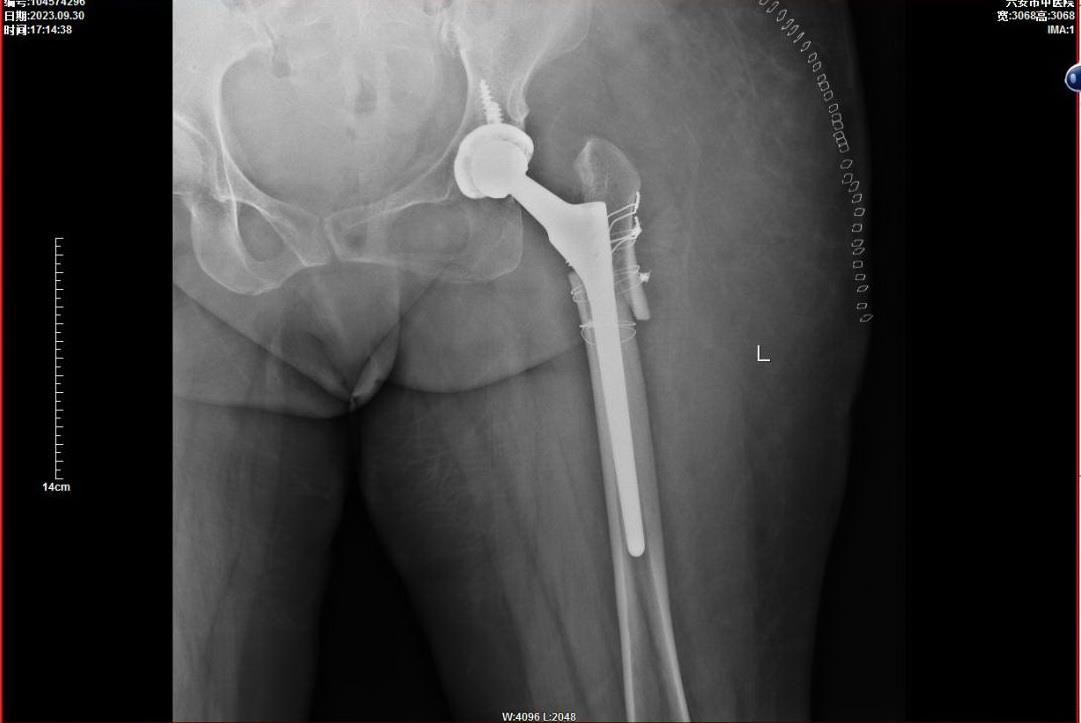

手术要把患肢延长,恢复两条腿等长,还要避免下肢延长造成血管和神经牵拉损伤,手术难度极大!

经过精心周密的术前准备,9月26号,张弢主任团队为她做了人工全髋关节置换手术,术后两条腿终于一样长了,而且活动自如!关节恢复到正常人的状态,下肢延长没有损伤血管神经! 结果让人欣喜!